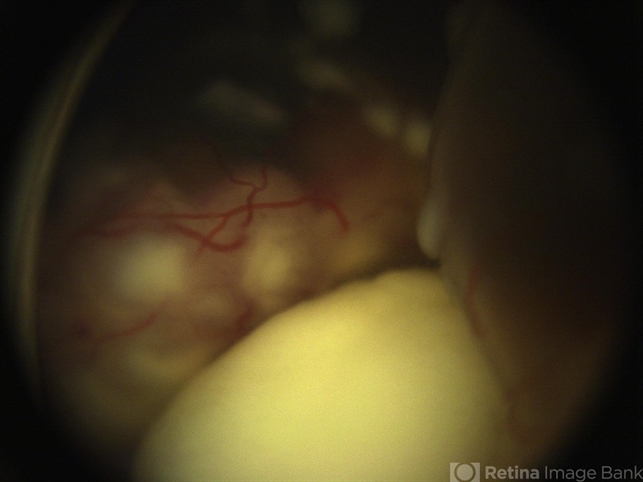

- retinoblastoma, tumor seeding

- Retcam Fundus photograph of a 3-year-old girl with no family history of retinoblastoma noted with a large retinal tumor with calcification filling 70% of globe with diffuse vitreous and subretinal seeding and exudative retinal detachment--unilateral Group E.